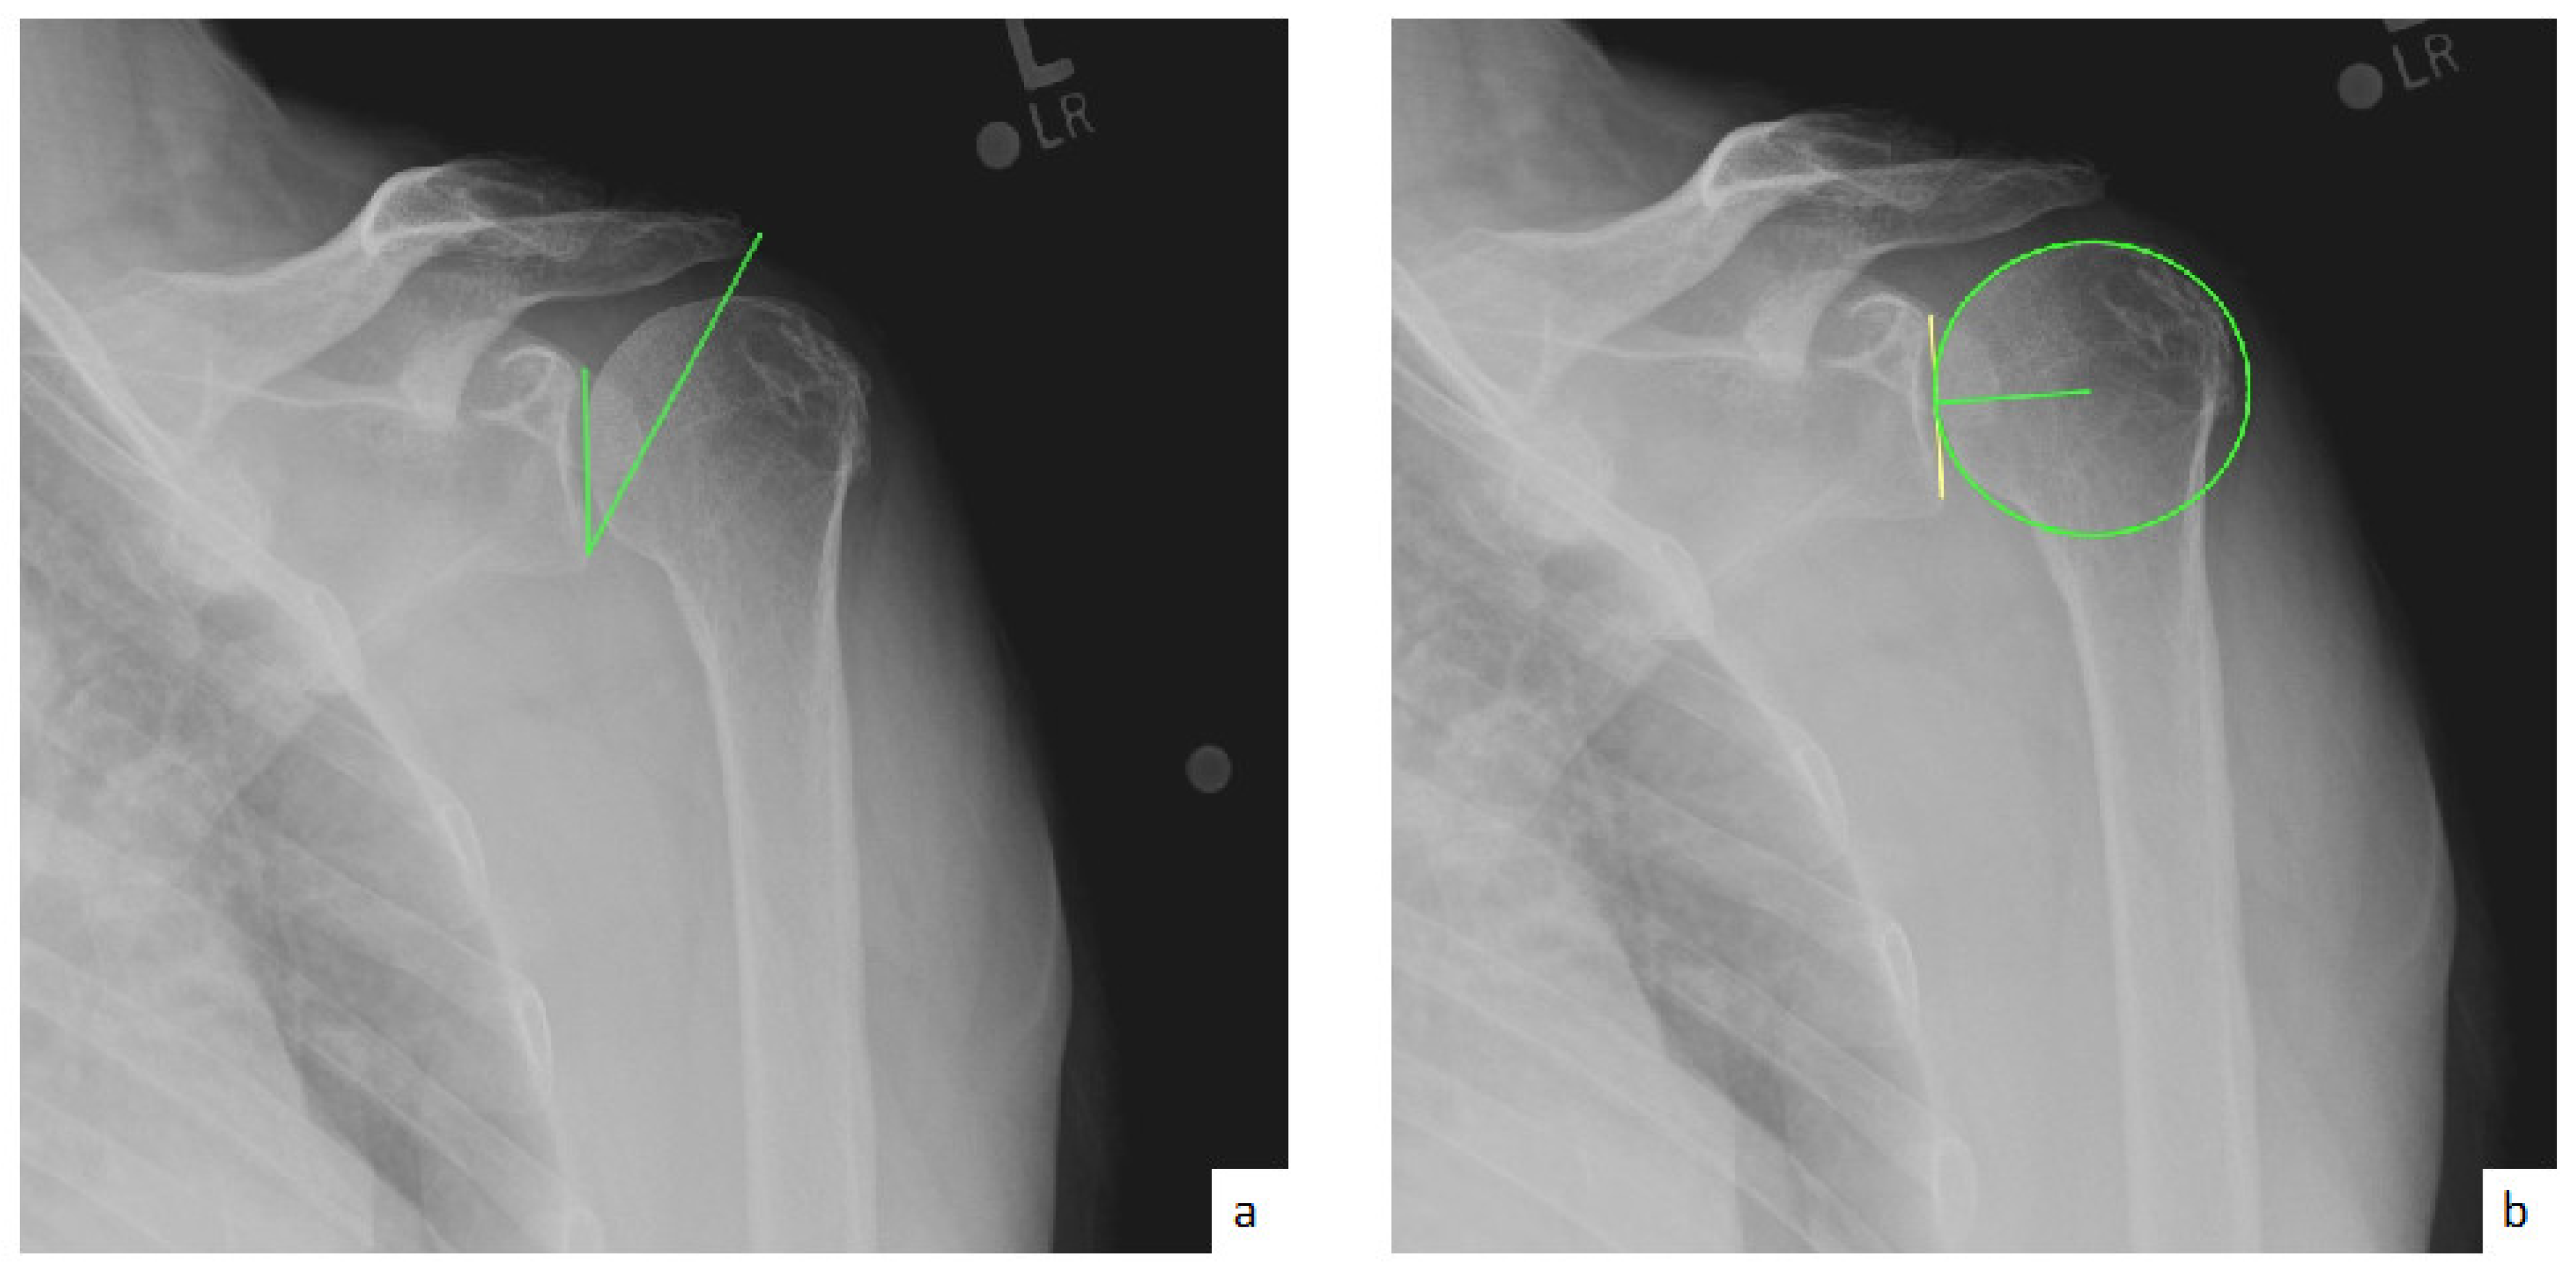

AHD was measured by calculating the perpendicular distance between the most lateral portion of the undersurface of the acromion and a line parallel to the superior border of the greater tuberosity [21] (Figure 1). LHO was measured by determining the distance from the AHD line to the most lateral projection of the greater tuberosity [21] (Figure 2). LSA was measured by drawing a line from the superior glenoid tubercle to the most lateral border of the acromion and a second line from the most lateral border of the acromion to the most lateral border of the greater tuberosity. The angle between these two lines formed the LSA [20] (Figure 3a). DSA was measured by drawing a line between the most lateral border of the acromion and the superior glenoid tubercle and drawing a second line to connect the superior glenoid tubercle with the most superior border of the greater tuberosity. The angle between these two lines formed the DSA [20] (Figure 3b). Glenoid and baseplate were determined as the angle between the floor of the supraspinatus fossa and the glenoid fossa [25] (Figure 4). COR was measured by determining the best fit circle flush to the articular surface, identifying the center of the circle in the humeral head, and then measuring the distance of the perpendicular line between the center of the humeral head and the midpoint of the line connecting the superior and inferior glenoid tubercles [24] (Figure 5b). CSA was measured by a line from the superior pole to the inferior pole of the glenoid and a line from the inferior pole to the lateral edge of the acromion [26] (Figure 5a). In addition, scapular notching was graded according to the Nerot–Sirveaux classification and severity of preoperative cuff tear arthropathy was evaluated according to the Hamada classification [27,28].

Figure 1.

(a) Preoperative acromiohumeral distance (AHD; green line); (b) postoperative acromiohumeral distance (AHD; green line).

Figure 3.

(a) Lateralization shoulder angle (LSA); (b) distalization shoulder angle (DSA).